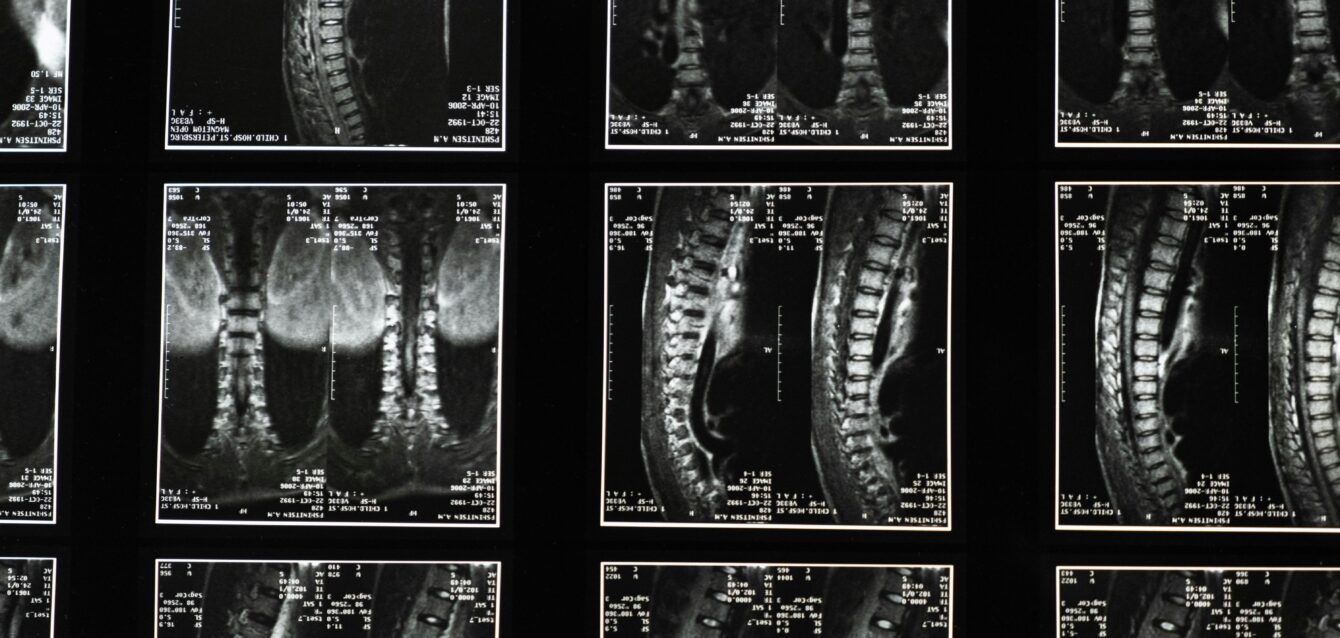

An innovative spinout from a prominent research institution needed a secure, browser-based solution to preprocess MRI data for deep learning analysis. The objective was to remove personally identifiable information (PII) from DICOM files and extract MRI images, ensuring compliance with privacy regulations. Their existing process lacked automation, leading to inefficiencies and potential data privacy concerns.

Accelvision designed and implemented a localized web application that allows users to upload DICOM files, automatically strip PII, and securely extract MRI images. This browser-based solution requires no additional software installations, offering a seamless and user-friendly workflow. It integrates with the client’s broader application, which leverages computer vision models to standardize spinal disc measurements and improve predictive analytics for surgical complications.